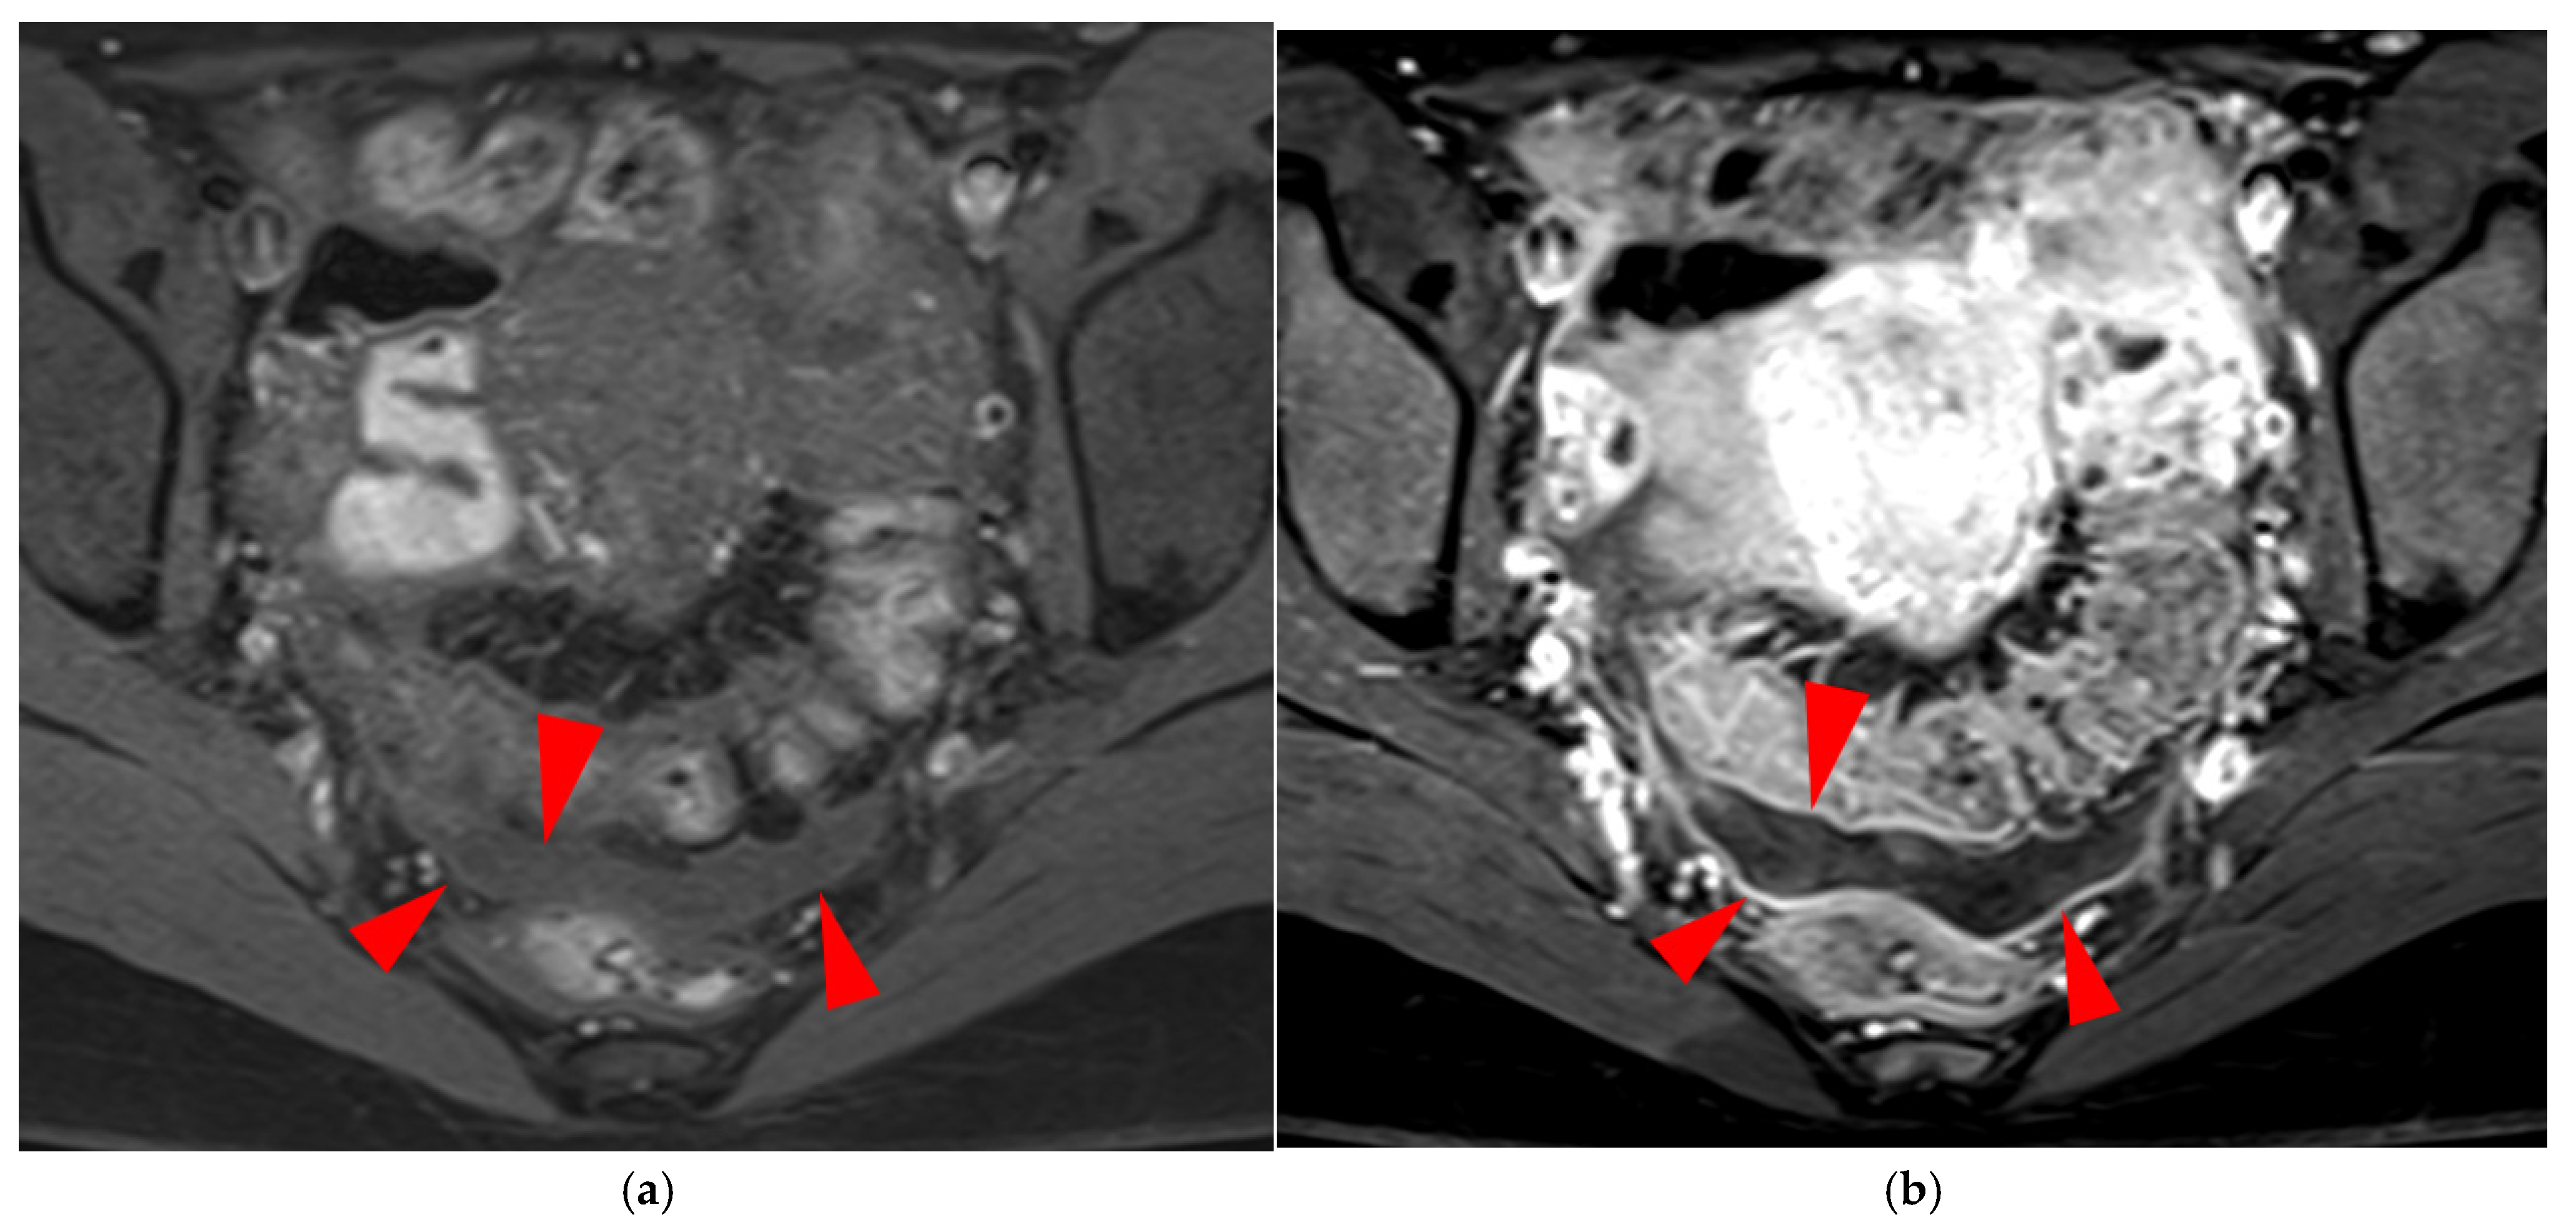

Figure 15. Pelvic MRI scan of a patient with a “kissing ovaries” sign and rectal involvement (i.e., HTD type 6 USLs). (a,b) Axial T2WI (a) and contrast-enhanced T1WI (b) show both ovaries in close proximity (“kissing ovaries” sign) (arrowheads) and rectosigmoid wall infiltration (arrows). (c) Sagittal contrast-enhanced T1WI shows rectosigmoid wall infiltration, appearing as a “medallion-shaped” lesion outlined by markedly enhancing mucosa (arrowhead).

Figure 17. Pelvic MRI scan of a patient with likely superficial endometriosis, performed during a painful menstrual period. (a) Axial fat-suppressed T1WI demonstrates moderate dependent peritoneal effusion (arrowheads). (b) Axial contrast-enhanced fat-suppressed T1WI reveals perceptible curvilinear enhancement of the peritoneal layers, suggesting the possible presence of superficial endometriotic lesions (arrowheads).

2.3.1. “Kissing Ovaries”: A Form Straddling Between Type 5B and Type 6 USLs

Besides endometriomas, another type of ovarian involvement in DIE includes adhesions that cause the ovaries to retract medially across the midline, behind the uterus, into the pouch of Douglas. When the ovaries are displaced medially and are in close proximity, they are commonly referred to as “kissing ovaries”. Additionally, medialized ovaries on preoperative imaging expose the digestive tract to a 20% risk of involvement [22]. In our experience, the injection of a contrast agent is useful when there is doubt about an endometriotic rectosigmoid invasive lesion on T2WI, especially if a rectal filling was not performed. A markedly enhancing mucosa, which outlines rectosigmoid local wall thickening on post-contrast T1WI without fat suppression (forming a “medallion-shaped” lesion), is a valuable aid to diagnosis.

In the HTD MRI classification of USLs, the “kissing ovaries” sign is considered a form between types 5B and 6. In the case of concomitant rectal involvement, the USL is classified as type 6 (Figure 15); otherwise, it is classified as type 5B (comparable to a nodule with spiculated margins).

2.3.2. Superficial Endometriosis

This form of endometriosis is not listed in the HTD MRI classification, as the classification focuses exclusively on DIE primarily involving the USLs. Regarding superficial endometriosis, MRI is not a reliable diagnostic tool. However, hemorrhagic peritoneal implants appearing as hyperintensities on fat-suppressed T1WI can be detected, particularly in dependent areas (Figure 16), and correlate well with superficial endometriosis at surgery [18,23]. In our experience, an indirect sign of superficial endometriosis that may be observed during painful menstrual periods is subtle inflammation of the pelvic peritoneal layers, appearing as a regular linear enhancement on contrast-enhanced fat-suppressed T1WI (Figure 17). This sign is non-specific but could serve as a useful indicator in the clinical context of cyclic pelvic pain suggestive of endometriosis. This enhancement on MRI may occasionally be accompanied by moderate dependent peritoneal effusion.